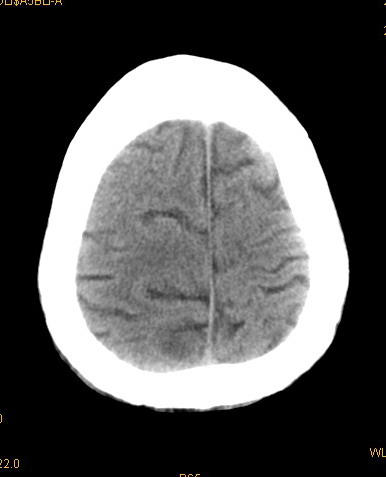

以下是引用卜一在2008-8-14 16:31:00的发言:[br]支持:巨脑回伴脑积水!另:胼胝体发育不良!

以下是引用随光逐影在2008-8-14 16:58:00的发言:[br]胼胝体发育不良;脑积水。

以下是引用同在2008-8-14 19:46:00的发言:[br]巨脑回伴积水,胼胝体发育不良.